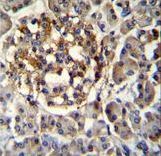

- Experimental details

- SEC14L5 Antibody immunohistochemistry of formalin-fixed and paraffin-embedded human pancreas tissue followed by peroxidase-conjugated secondary antibody and DAB staining.